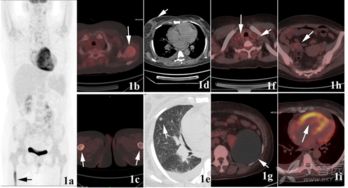

惡性腫瘤細(xì)胞由于代謝旺盛而對(duì)葡萄糖的需求增加,因此18FDG后,大多數(shù)腫瘤病灶會(huì)表現(xiàn)為對(duì)18FDG的高攝取,因此可應(yīng)用18FDG

PET-CT顯像可早期發(fā)現(xiàn)全身腫瘤原發(fā)及轉(zhuǎn)移病灶,準(zhǔn)確判斷其良、惡性,從而正確指導(dǎo)臨床治療決策。但是18F-FDG有著放射性核半衰期,這就總讓受檢者們擔(dān)心,做完P(guān)ET